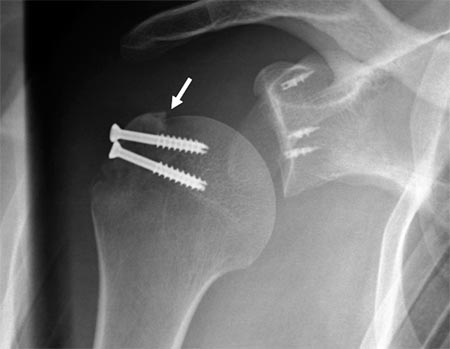

Si la reducción de los fragmentos es correcta en las imágenes por radioscopía, la fijación temporal de los fragmentos óseos con clavijas percutáneas es llevada a cabo. Posteriormente y según el tamaño de los fragmentos se utilizan tornillos canulados de 2.7 mm, 3,5 mm y/o 4.5 mm. Es importante remarcar nuevamente la no resección de los tejidos blandos (manguito rotador) de los fragmentos óseos. En 4casos de fracturas conminutas la reducción y osteosíntesis de los fragmentos fue lograda a través de los tejidos blandos y no del propio tejido óseo. Si la reducción de los fragmentos no es correcta la inspección del lecho de la fractura, primero a nivel articular y luego a nivel subacromial, es llevada a cabo con el fin de facilitar la misma mediante la remoción de tejidos interpuestos. En todos nuestros pacientes fueron colocados no menos de 3 tornillos de fijación (Fig. 1 y 2).

Figura 1C: Espacio subacromial. Reducción artroscópica fractura del troquíter. Se observa línea de fractura./ Figura 1D: Osteosíntesis artroscópica con tornillos canulados de 3.5 mm./ Figura 1E: Reducción y ostesíntesis con 3 tornillos canulados de 3.5 mm. Flecha: pérdida de hueso. Reparación de Bankart y SLAP asociada.

Figura 2D: Flecha negra: Clavija percutanea mantiene la reducción. Flecha Amarilla: línea de fractura./ Figura 2E: Osteosíntesis con tornillo canulado de 3.5 mm./ Figura 2F: Resultado. Escalón superior de 2 mm. Reparación de Bankart y SLAP.

La evaluación radiográfica realizada inmediatamente posterior a la cirugía dejó en evidencia un promedio de desplazamiento del troquíter en relación a la cabeza de 2.8 mm(rango 1.2 mm - 4 mm). La posibilidad de evaluar preoperatoriamente el dolor, rango de movimiento y los tests deRowe y Ases se vio dificultada por el intenso dolor que referían los pacientes. Al final del seguimiento de cada paciente y según la escala visual analógica el promedio de puntuación para el dolor fue de 1.1 (rango de 0 – 3). El promedio del test de Ases fue de 95.3 y el promedio del test de Rowefue de 91.3. Ocho pacientes presentaron resultados excelentes (90-100) y dos pacientes resultados buenos (89-75). Todos los pacientes presentaron signos de consolidación entrelas 8 y 15 semanas. A los 18 meses el promedio de elevacióndel hombro fue de 174.7 grados (rango 166 -180). El promedio de rotación externa con el codo al cuerpo fue de 61grados (rango 48-75). En cuanto a la rotación interna: seispacientes alcanzaron el nivel T7, dos el T8, uno el T9 y unoel T10 respectivamente (Tabla 1).